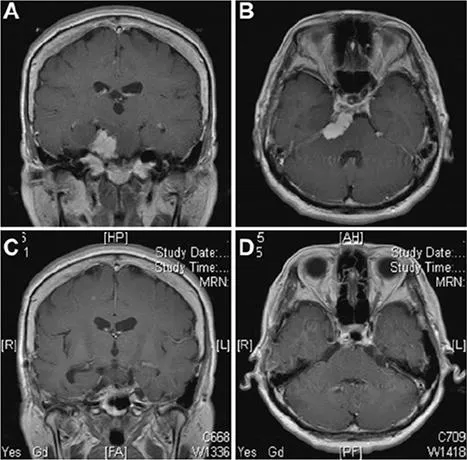

53岁女性患者,表现为搏动性头痛,并发现左眼视力急剧下降。MRI显示岩斜上交界处存在一均匀强化的肿块,广泛附着于上斜坡和天幕(图A和B)。采用Kawase入路进行手术。在滑车神经入幕附近行小脑幕切口后,可见三叉神经向双侧下移位,部分被肿瘤包裹,与上斜坡相连,且部分钙化。外展神经在肿瘤切除后观察到向下移位。术后MRI(图C和图D)显示肿瘤完全切除,无脑组织损伤。患者术后出现部分侧视麻痹,1个月后完全消失,功能恢复正常。

图示:术前图像(A和B)提示岩斜区均匀强化肿瘤,起源于岩尖,附着于小脑幕。肿瘤推挤脑干,侵犯海绵窦。术后(C和D)显示肿瘤全切。